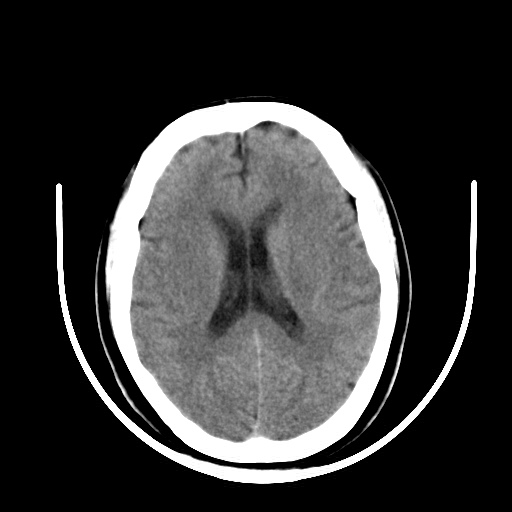

标题: CT16579:女 65岁间断性抽搐. [打印本页]

标题: CT16579:女 65岁间断性抽搐.

考虑右侧颞叶脑软化灶并脑穿通畸形;建议必要时行进一步检查。

右侧蛛网膜囊肿

右颞叶脑软化灶。余未见明显异常。

考虑右颞叶脑软化灶

右颞叶软化灶,右基底节区腔隙性脑梗塞;